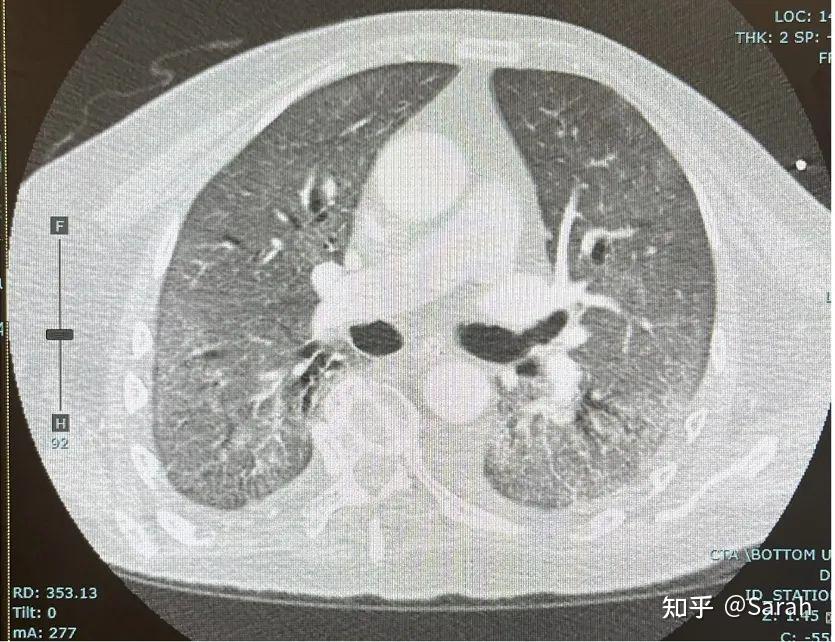

图4:疫情早期的新冠ICU场景逼到各医院都没办法了。后来,从我们医院开始,每天交接班的第一件事就是先组织一个「俯卧小组」,八九位护士一起,一个人护住患者的头,其他人一起来给这位患者做俯卧,使用各种楔状海绵在体位两侧保护皮肤受压区,现在,哪个医院也不用旋转床了,想借旋转床发财的人竹篮打水一场空。回到病例,突然缺氧患者必须要做CTPA,排除肺栓塞。栓塞倒是没有,可现在的肺野影像是这样的:(图5)

图5:肺水肿CT影像与前面(图1)我所选的影像对比可以看到,现在的特征仍然是毛玻璃影,但是却是同质的毛玻璃影,不是片状的,而且整个两侧肺野都是这样,另外,在下肺野处明显有六角线出现,术语为小叶间隔增厚,表示淋巴液流量增加。在这种情况下,基本上可以根据这份CT确定是「肺水肿」的情况。肺水肿怎么来的? 要做一些分析:1、前24小时的输入量和输出量,这位患者的输入量是1.7升,为了做CTPA、为了保护肾脏,又给了另外500毫升生理盐水点滴,整体的净输入量大概是2.2升。另外,做重症的医生都得会做点超声。凭肉眼估计,这位患者的射血分数大概45%(患者基线为70%)。因此,患者带一点心源性原因、又有体液过度(水钠潴留),共同造成了肺水肿的发生。这时还做了血液检查,炎症指标并没有什么变化,心肌酶进一步降低了,淋巴细胞反而比原来正常了一点,其他的肝功能和乳酸也没有什么大区别。怎么造成的肺水肿?心肌炎吗?目前还没有让人信服的证明,现在的倾向认为是「应激性心肌病」,要比心肌炎常见的多。处理应急性心肌病与心肌炎不同,预后也不一样。另外就是「多系统炎症综合征(MIS)」,MIS也是一种炎性反应,它的特征是发热,大血管炎,累及冠状动脉、主动脉、肾动脉,还有胃肠动脉,所以当患者表现出胃肠症状时,一定要判断是不是MIS。这位患者很显然可能性不大,因为没有明显胃肠症状,关键是没有发热,炎性反应因子相比原来有改善了,并没有增高。这时,我们给他静脉注射了40毫克速尿,他一下排了差不多一升的尿,这也不用再做其他检查了,因为氧合很快改善了。做这个报告时,患者已经脱机了、不再气管插管,可见后面的病情反复是因为水液潴留,并不是因为新冠。最近很多同行问,新冠康复后咳嗽,这是不是叫「长新冠」?已经有很多的文献证明,这叫「感染后气道高敏感性咳嗽,PIHA」。PIHA最早的报告是90年代,见于呼吸道感染痊愈后的持续性激惹性咳嗽。不仅见于新冠,不代表活动性感染,而是感染造成了气道上皮细胞破坏,使平滑肌细胞敏感,所以稍微一点冷空气都能引起咳嗽。最常见的原因就是各种病毒感染导致的,这并不是新冠特异的表现。在上世纪90年代,刚开始报告这种情况时,根据气道分泌物DNA测试,曾经怀疑是不完整的百日咳杆菌感染,特征就是呼吸道感染痊愈4个星期后还在咳嗽。PIHA性质是良性的,最后都会恢复,一般需要4-6个月才能彻底恢复,这种咳嗽很令人难受,我们给患者的处理基本和哮喘相似,即使用支气管扩张剂。当时怀疑是百日咳时,曾经提倡采用红霉素。即使后来大家发现百日咳证据不足,我处理这种情况仍然觉得红霉素有效,为什么?因为红霉素具有非特异性的、抑制气道平滑肌炎症反应的作用。这一作用最早由日本人在限制性小支气管炎患者见到,现在连慢阻肺病,囊性纤维化等情况的患者都提倡用红霉素。其实不做治疗的话,患者自己也会好,但用点药,患者会很快见好。此时患者会觉得你「是有两下子」。专家简介